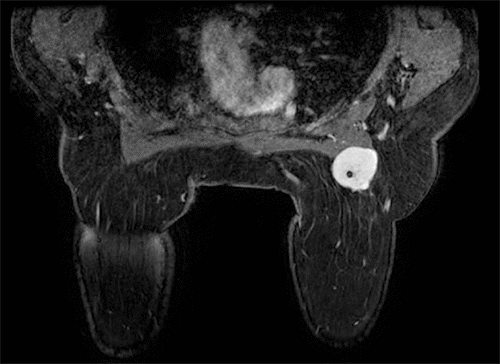

The core needle biopsy slides from the outside facility were submitted for second and third opinions to our institution's pathology department and Memorial Sloan Kettering, which confirmed metastatic sarcoma. She then underwent a bilateral breast magnetic resonance imaging (MRI) (Figure 1) as well as a whole-body positron emission tomography (PET) scan. PET scan showed mild uptake (1.5 standard uptake value [SUV]) of a 9 mm nodule in the right lower lobe of the lung (Figure 2) as well as in the right breast mass. After a multidisciplinary tumor board discussion, it was decided that surgical excision of the breast mass with a sentinel lymph node biopsy would precede chemotherapy. While there is little evidence for lymph node metastasis in liposarcoma, a sentinel node biopsy was performed for a more thorough approach to the breast lesion. The medical oncology team agreed this would be an appropriate course, given that her sub-centimeter pulmonary nodule did not necessarily mandate systemic treatment in the neoadjuvant setting. Moreover, the patient herself was very motivated to have her mass removed as it was causing her pain and discomfort.

Figure 2. Bilateral breast MRI with intravenous (IV) contrast Sagittal T2 STIR sequence. Published with Permission

Image depicts right breast mass with intimal connection with pectoralis muscle, 3.0 × 3.5 × 4.5 cm, very dense lobulated mass with postbiopsy clip marker

Figure 3. Axial PET/CT Fusion. Published with Permission

Well-circumscribed, round 9 mm right lower lobe mass (arrow) with mild increased FDG uptake; SUV max 1.5, concerning for metastatic deposit